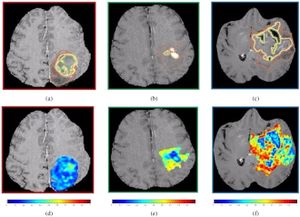

Detectability of Radiation-induced Changes in Magnetic Resonance Biomarkers following Stereotactic Radiosurgery: A Pilot Study

Publication: PLoS One. 2018 Nov 26;13(11):e0207933. PMID: 30475887 | PDF Authors: Winter JD, Moraes FY, Chung C, Coolens C. Institution: Radiation Medicine Program, Princess Margaret Cancer Center and University Health Network, Toronto, Ontario, Canada. Abstract: Our objective was to investigate direct voxel-wise relationship between dose and early MR biomarker changes both within and in the high-dose region surrounding brain metastases following stereotactic radiosurgery (SRS). Specifically, we examined the apparent diffusion coefficient (ADC) from diffusion-weighted imaging and the contrast transfer coefficient (Ktrans) and volume of extracellular extravascular space (ve) derived from dynamic contrast-enhanced (DCE) MRI data. We investigated 29 brain metastases in 18 patients using 3 T MRI to collect imaging data at day 0, day 3 and day 20 following SRS. The ADC maps were generated by the scanner and Ktrans and ve maps were generated using in-house software for dynamic tracer-kinetic analysis. To enable spatially-correlated voxel-wise analysis, we developed a registration pipeline to register all ADC, Ktrans and ve maps to the planning MRI scan. To interrogate longitudinal changes, we computed absolute ΔADC, ΔKtrans and Δve for day 3 and 20 post-SRS relative to day 0. We performed a Kruskall-Wallice test on each biomarker between time points and investigated dose correlations within the gross tumour volume (GTV) and surrounding high dose region > 12 Gy via Spearman's rho. Only ve exhibited significant differences between day 0 and 20 (p < 0.005) and day 3 and 20 (p < 0.05) within the GTV following SRS. Strongest dose correlations were observed for ADC within the GTV (rho = 0.17 to 0.20) and weak correlations were observed for ADC and Ktrans in the surrounding > 12 Gy region. Both ΔKtrans and Δve showed a trend with dose at day 20 within the GTV and > 12 Gy region (rho = -0.04 to -0.16). Weak dose-related decreases in Ktrans and ve within the GTV and high dose region at day 20 most likely reflect underlying vascular responses to radiation. Our study also provides a voxel-wise analysis schema for future MR biomarker studies with the goal of elucidating surrogates for radionecrosis. "To enable spatially registered voxel-wise analyses, we developed a rigorous in-house registration pipeline to perform all image registration steps as well as visualize image registration results using Python (Python Software Foundation), interacting with 3D Slicer." Funding: